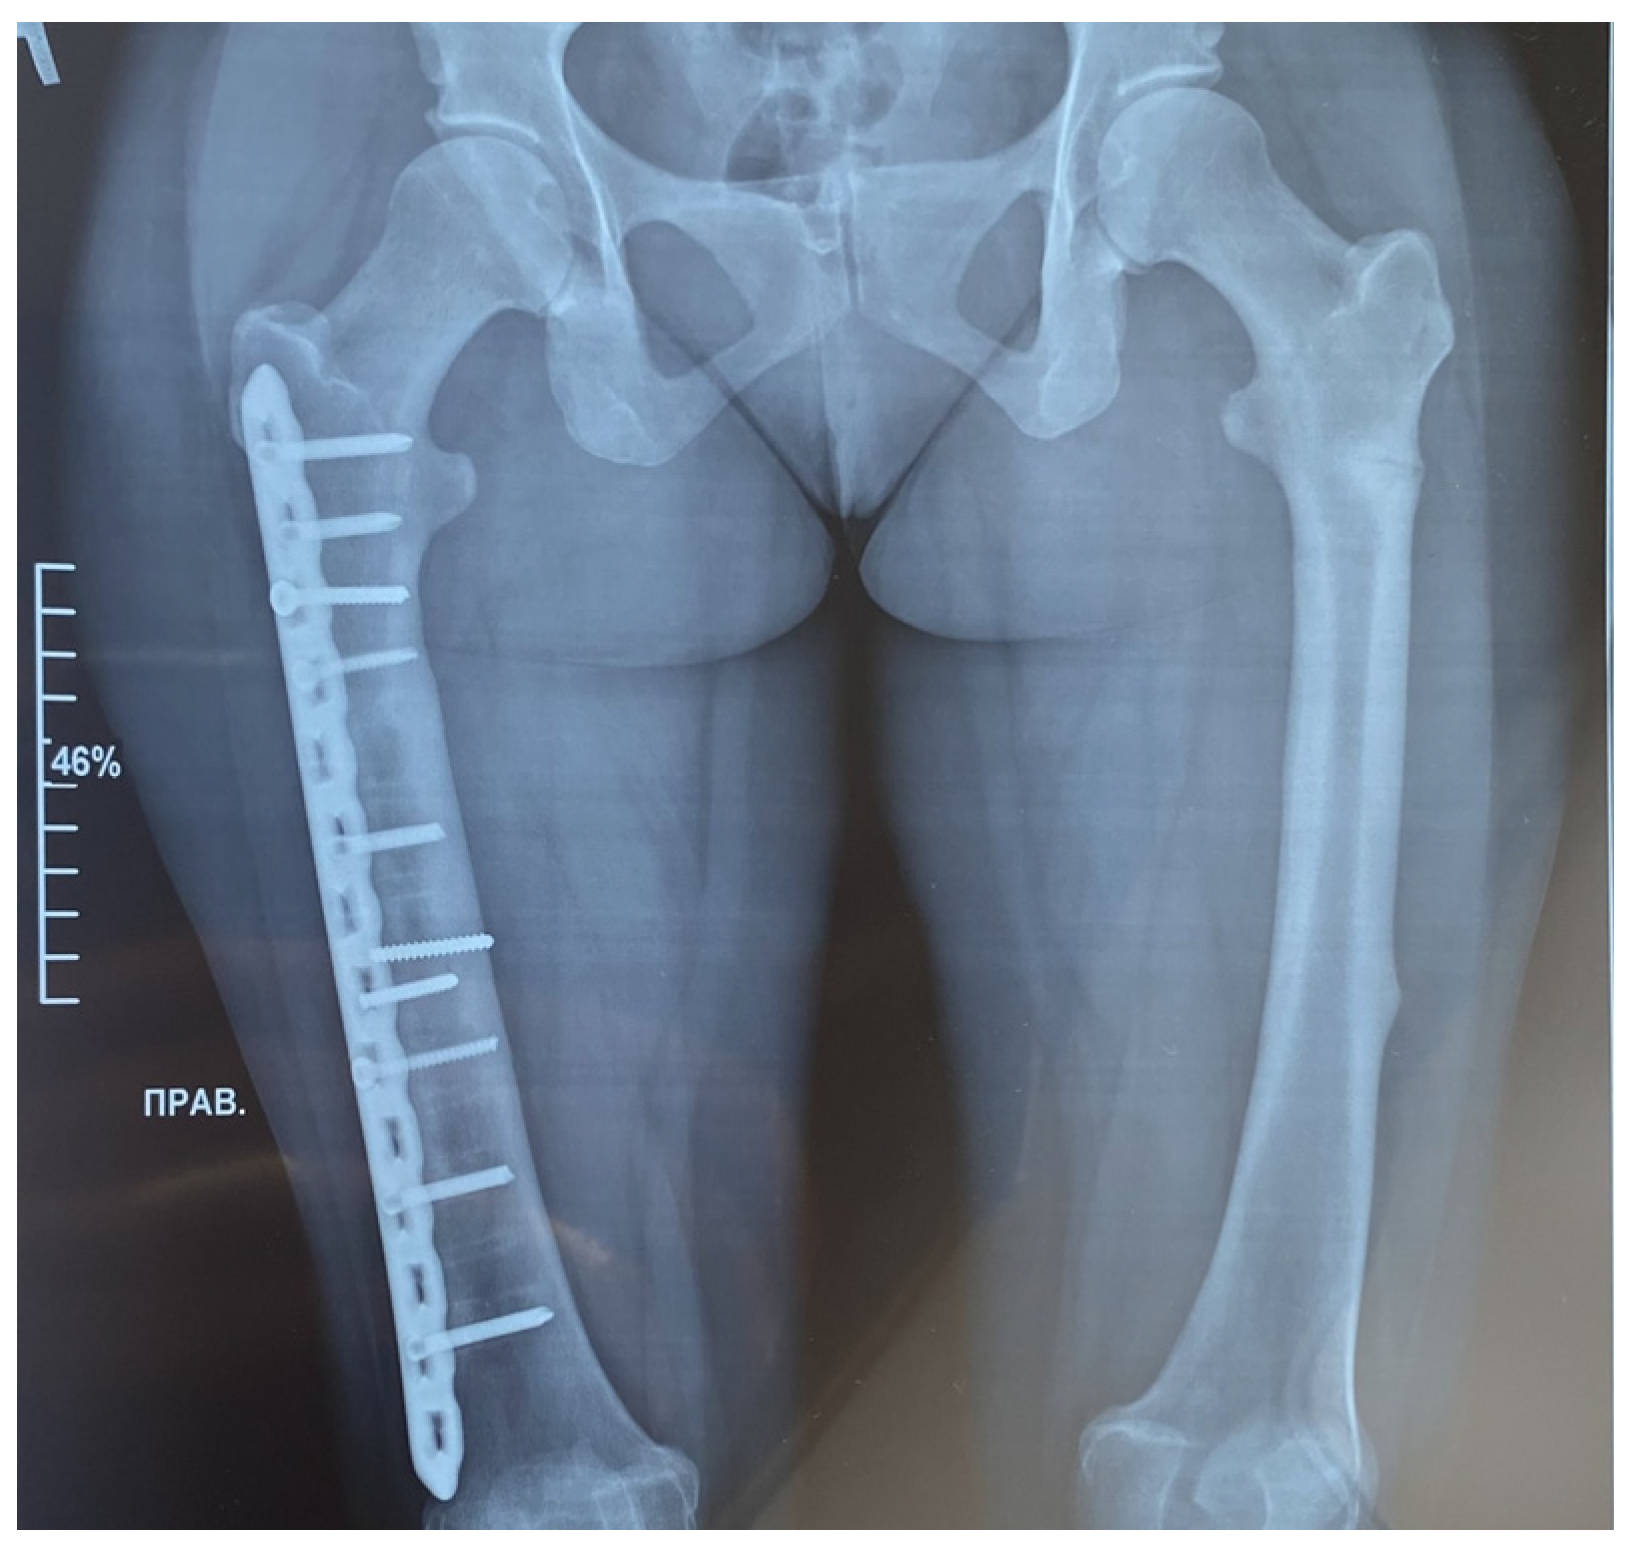

| 8 | 32 years old | Closed transverse fracture with displacement of fragment | the middle third of the right femur |

| 9 | 37 years old | Closed peri-implant fracture with displacement of fragment | the right femur |